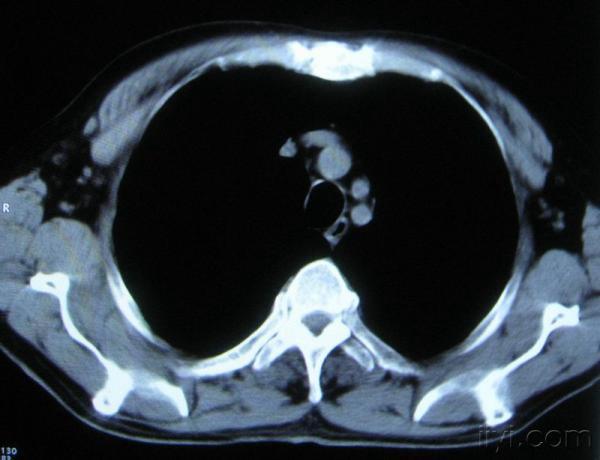

你指那个肯定是淋巴结,中央系坏死,这很常见,特别在双侧腹股沟会经常看到。这个双侧腋窝及纵隔见多发小淋巴结征。

根据位置考虑应该是淋巴结,密度不均,是因为肿大的淋巴结中心液化坏死